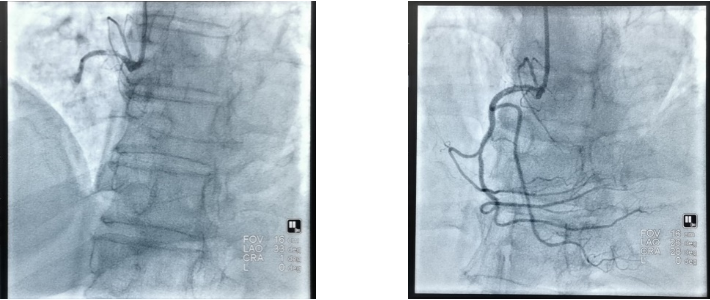

病例一:86岁高龄男患,术前造影显示右冠状动脉血管急性完全闭塞(左图)。顺利开通患者闭塞的血管,造影显示支架置入成功恢复右冠状动脉血供(右图)。